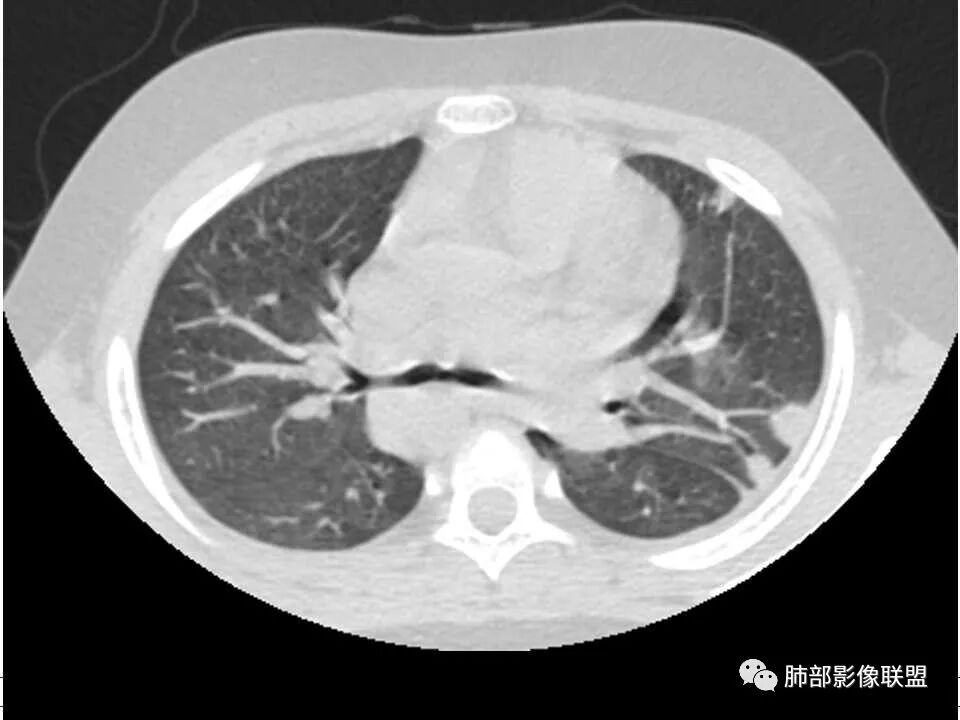

晨读,儿童,起病急,病程短,有下肢疼痛伴肿胀病史,发热,白细胞升高,结合下肢辅查,考虑骨髓炎,胸部ct:双肺多发空洞,结节,外带下叶为主,空洞内外光滑,无丝状物,有血管滋养征,综合病史及影像考虑脓毒性肺栓塞,金葡可能性大,建议痰培养,血培养,必要时ngs。

儿童患者,右下肢肿痛、发热起病,血象升高,双肺多发结节影,右肺结节并囊腔或空洞,左肺多发实性结节以胸膜下分布为主,考虑感染性病灶,有右下肢肿胀,需考虑蜂窝织炎, 血源性肺播散,金葡感染可能性大?

双肺多发空洞、结节及胸膜下楔形密度增高影,结合临床考虑:1.金葡菌肺感染。2脓毒性肺栓塞。

双肺多发结节,空洞,与胸膜相连,血道来源,空洞内壁光滑,结节周围模糊,考虑金葡菌感染。

患者儿童,因右下肢疼痛伴肿胀14天就诊。病程中有发热及伴随症状。膝关节MRI提示右侧膝关节及右髌骨髁异常信号影,右膝髌上囊及关节腔内少量积液。胸部CT:双肺胸膜下多发结节影,部分结节空洞形成,且结节周围可见血管集束征。综合考虑血源性脓毒性肺栓塞、坏死性肺炎。右侧骨髓炎、血播性金葡菌肺炎,鉴别其他特殊感染及血管炎。

胸部ct:双肺多发空洞,结节,外带下叶为主,空洞内外光滑,有血管滋养征,综合病史及影像考虑脓毒性肺栓塞,结合病史,金葡可能性大。

小儿,急性起病,下肢疼痛,mr提示骨髓水肿,临床化验炎性指标高,考虑金葡菌骨髓炎,双肺多发结节,以血管支气管束及胸膜下分布为主,部分结节近端与血管相连,部分结节可见空腔,内壁光整,部分囊腔有张力,考虑骨髓炎并肺内血播感染,金葡?

2.双肺多发片影,随机分布,多空洞或囊腔,胸膜下多楔形影,气道未见受累等等符合脓毒血症影像学表现,尤其是金葡。